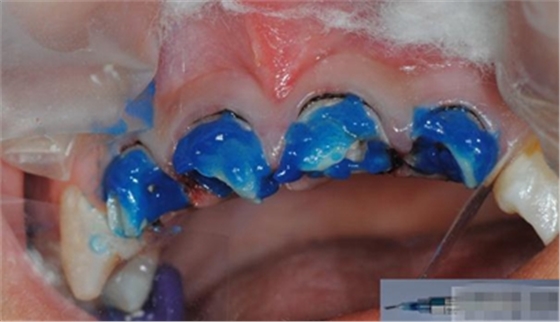

【酸蝕粘結(jié)】

使用磷酸酸蝕可用完全去除玷污層,粘結(jié)劑可用充分滲透到牙本質(zhì)小管中。用自酸蝕系統(tǒng)則達(dá)不到這一點(diǎn),由于其不能充分去除玷污層,粘結(jié)劑向牙本質(zhì)小管內(nèi)的滲透率低。所有的研究均顯示,使用全酸蝕系統(tǒng)所形成的粘結(jié)混合層要比使用自酸蝕系統(tǒng)厚。

沖洗注意點(diǎn):

1.酸蝕后沖洗時(shí)間要充分,最少20s---1min(沖洗時(shí)間>酸蝕時(shí)間)2.沖洗不要用自來(lái)水,相當(dāng)于二次污染 3.不含油霧壓縮空氣吹干牙面

組織過(guò)于干燥會(huì)影響粘結(jié)效果。而且通常也會(huì)導(dǎo)致術(shù)后敏感。酸蝕后牙本質(zhì)不應(yīng)吹干。沖洗掉酸蝕劑后洞型用氣槍吹干,但要組織保持濕潤(rùn)非常重要。牙本質(zhì)看起來(lái)應(yīng)該是反光的,而不是白堊狀。

將粘結(jié)劑在牙體硬組織上充分涂布20秒,最少2次,然后,輕輕吹干,固化。理想的粘接劑的厚度不應(yīng)超過(guò)50微米。如果粘接層過(guò)后可能會(huì)發(fā)生微滲漏,過(guò)薄則可能彈性不足。飽和粘接系統(tǒng)第一層厚度可以達(dá)到30-40微米,有時(shí)也會(huì)超過(guò)此值。但這個(gè)厚度對(duì)于一些情況不適用,如嵌體粘結(jié)。80-100微米厚度的粘接層難以形成持久的固位力。電子顯微鏡照片顯示飽和粘接系統(tǒng)會(huì)形成較厚的粘接層,并且,其內(nèi)部充滿氣泡,optibond和PQI就屬于飽和粘結(jié)系統(tǒng)。Dr.Vanini的建議最好使用不飽和粘結(jié)系統(tǒng),因?yàn)?,飽和粘結(jié)系統(tǒng)往往會(huì)形成過(guò)厚的粘結(jié)層。Dr.Vanini使用ENA bond粘接系統(tǒng),在單層應(yīng)用時(shí)厚度為8微米,2層為12微米,3層為25微米。三層粘結(jié)劑所形成的粘接力值可以達(dá)到49MPa(N/平方MM)。使用非飽和粘結(jié)系統(tǒng)進(jìn)行2-3層的粘接方法的另一個(gè)優(yōu)點(diǎn)是可以減少術(shù)后過(guò)敏癥狀的出現(xiàn)。